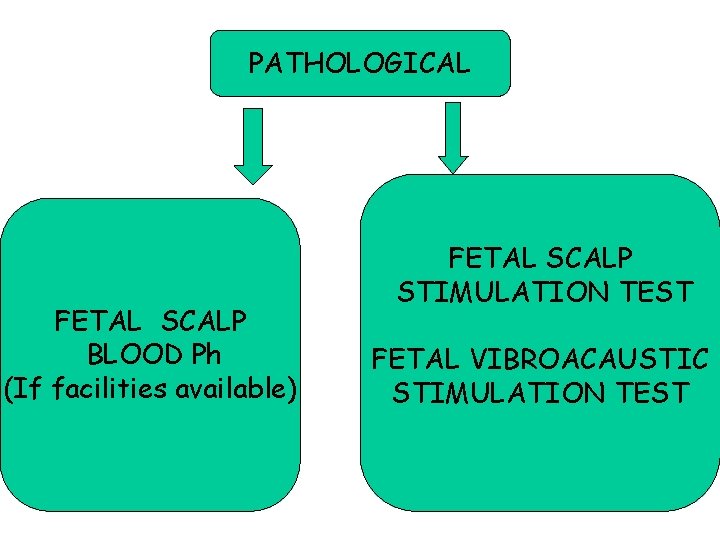

PATHOLOGICAL FETAL SCALP BLOOD Ph (If facilities available) FETAL SCALP STIMULATION TEST FETAL VIBROACAUSTIC STIMULATION TEST 65